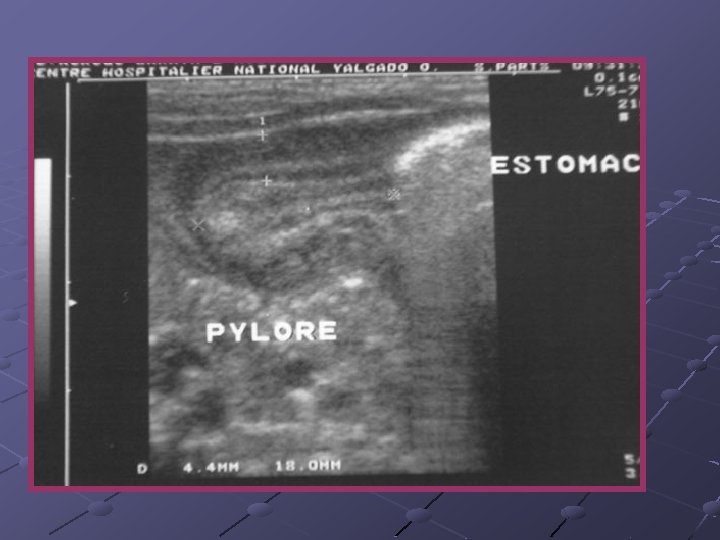

Cas n° 5 17 mois Histoire médicale antérieure = o Pleurs, douleurs abdominales

3, 7 x 2, 8 cm Depuis le rectum hypochondre gauche

INVAGINATION INTESTINALE AIGUE (IIA) Télescopage et penetration d’ un segment intestinal dans le segment d’ aval. Urgence diagnostique et thérapeutique: compression vasculaire ischémie et nécrose Nourrisson ( 80 % entre 6 mois et 2 ans ). Maximum entre 4 et 12 mois (I). Avant 3 mois ou après 5 ans (II). Prédominance masculine ( 3 G/2 F).

Idiopathique ( 90% des cas ): adénolymphite mésentérique(caractère saisonnier ) Secondaire: lymphome digestif, meckel, duplication digestive , polype , purpura rhumatoïde , troubles fonctionnels post chirurgicaux , impactions digestives ( mucoviscidose. . ) Formes anatomiques: iléo-iléale n iléo-colique n Appendico-colique n colo-colique n diam. boudin < 20 mm diam. boudin > 25 mm Diagnostic = échographie et non l’ASP Traitement: - Lavements (air, hydrosoluble, eau) - Chirurgie Contre-indications des lavements: péritonite, choc